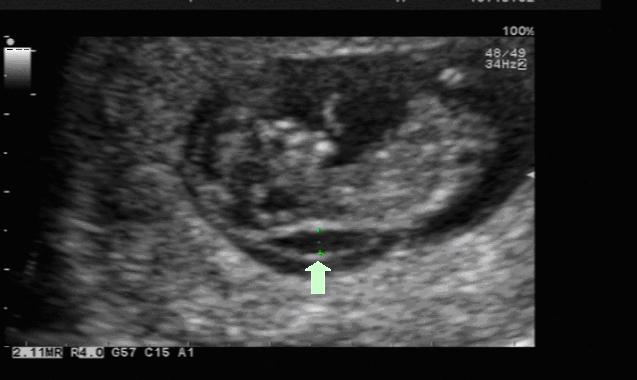

NT是胎儿颈部透明层(nuchal translucency)的英文缩写。胎儿颈后透明层(NT)是胎儿颈项部皮下的淋巴液聚集的部位,在超声影像中,是一条暗带,通过超声测量胎儿矢状切******肤至皮下软组织之间的厚度,可以用于评估胎儿是否有可能患有唐氏综合征。所有胎儿的NT值都有一定的厚度,不过,多数有唐氏综合征胎儿的NT值更厚。

图1:NT正常的胎儿(箭头所指处即为NT) 图2:NT增厚的胎儿(箭头所指处即为NT)